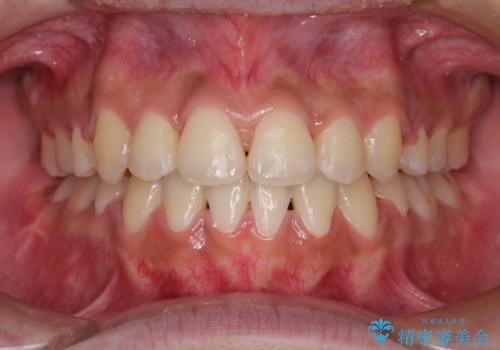

上下の正中位置が大きくずれていたため、治療期間の長期化や正中が合わないまま終了することが予想されましたが、思っていた以上にスムーズに歯が移動し、満足いただける仕上がりとなりました。